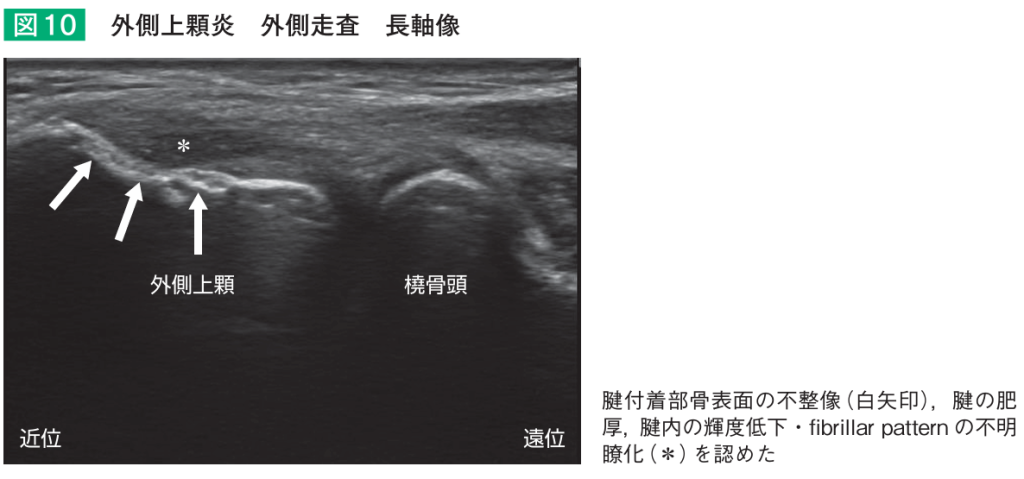

テニス肘・上腕骨外側上顆炎

肘の外側のスジ(腱)が骨にくっついている所の炎症により、肘の痛みを生じる病気をテニス肘、正式名称で上腕骨外側上顆炎と言います。好発年齢は30歳代の後半から50歳代で、テニスやバドミントンなどのラケットスポーツをやっている人に起きやすいです。フライパンや椅子など少し重いものを持つと肘の外側が痛くなるのが特徴です。

テニス肘・上腕骨外側上顆炎の診断

診察では肘のスジの付着部を軽く押したり、手首を反らして肘の痛みが生じるかを確認します。またレントゲンで肘の変形がないかを確認し、エコーでスジが腫れてたり痛んでいたら(下の図)、診断が確定します。

- 肘関節における超音波診療. 横山賢二1,松浦哲也. 関節外科 Vol.40 10月増刊号(2021)